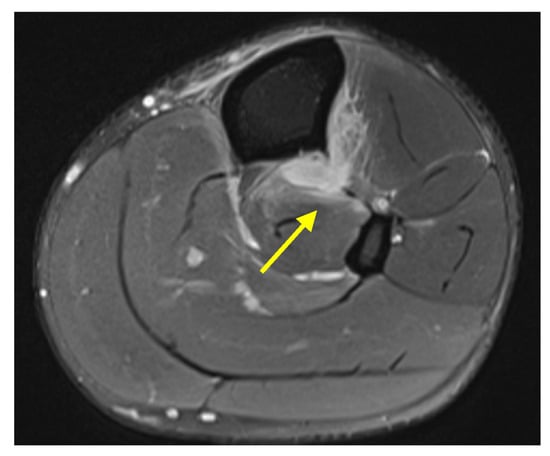

Case 1: A 22-year-old male professional basketball player presented with right leg pain after running into a camera man during a game. He experienced immediate leg pain and swelling. He had no prior history of trauma to this area. Physical exam revealed ecchymosis and swelling about the anteromedial aspect of the tibial midshaft with tenderness to palpation. Radiography was unremarkable. MRI revealed a focal tear of the tibiofibular IOM at the level of the mid tibia (Figure 1). No concurrent ligamentous or osseous injury was identified.

Figure 1. Case 1. Axial proton density fat-saturated MR image from a 22-year-old man with focal tear of the tibiofibular IOM at the level of the mid tibia (yellow arrow).